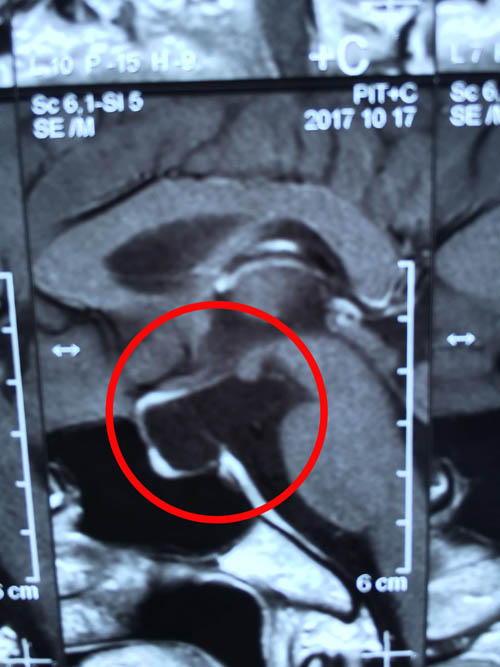

清晰影像之下 “元凶”无可遁形(红圈内即为垂体柄囊肿)